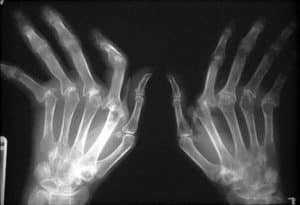

Arthrose, déformation des doigts et articulations

Déformation des doigts et méthodes naturelles

Il existe de nombreuses méthodes naturelles pour soulager la déformation des doigts. Je n’en livrerai ici qu’elle seule : passer les mains dans des graines de colza chaque jour diminue la déformation et les douleurs des doigts.